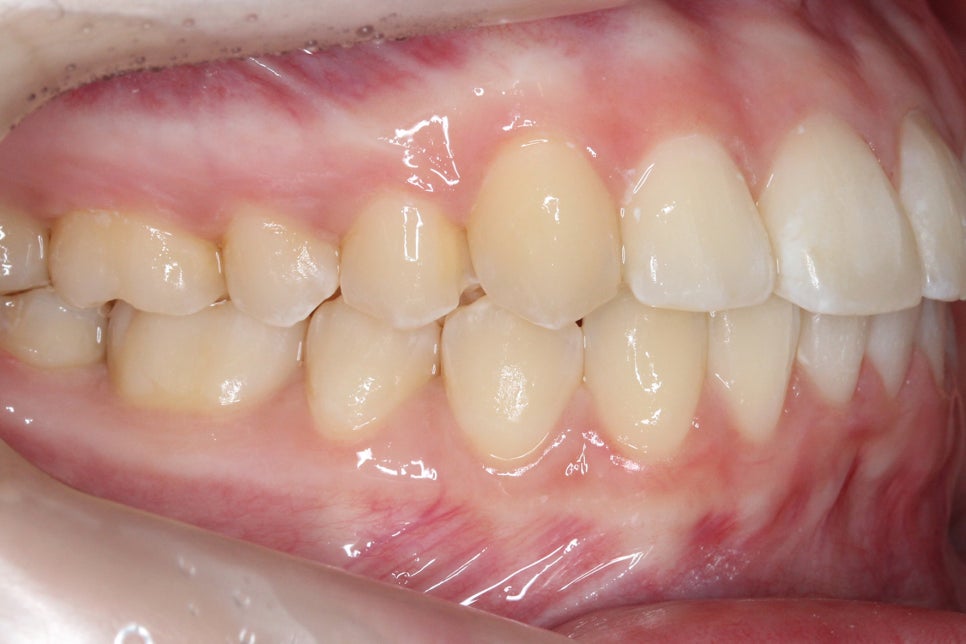

송곳니덧니 교정 전 상악의 치아 배열을 보면

전체적으로 좁고 긴 안모의 모습을 하고 있는데요,

순측으로 뻐드러져 있는 견치를 바른 각도로

조정하기 위해서 구치부 치아를 이동시켜

공간을 확보해야 할 것으로 보입니다.

상악의 경우 교합면을 보면

교정 전 송곳니가 순측으로

뻐드러지듯 튀어나가 있던 모습에서

클리피씨교정 후 바른 위치로

바뀐 모습을 확인할 수 있는데요,

치아의 위치가 바르게 바뀌면서

전체적인 안모의 형태도

부드러운 u-라인을 형성한 모습입니다.